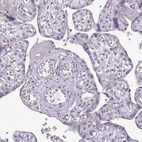

Immunohistochemical staining of human heart muscle shows moderate cytoplasmic positivity in cardiomyocytes.